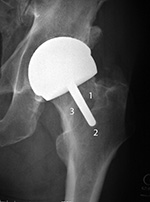

| Bipolar hemiarthroplasty (prosthesis) |

Bipolar hemiarthroplasty (prosthesis) |

Bipolar hemiarthroplasty (prosthesis)

| A free riding acetabular cup is press fit into the native acetabulum. The acetabular cup articulates with a prosthetic femoral head and stem component. From Benjamin, 1994 |

From Benjamin, 1994 |

92 year-old woman treated for left femoral neck fracture. From Taljanovic, 2005 |